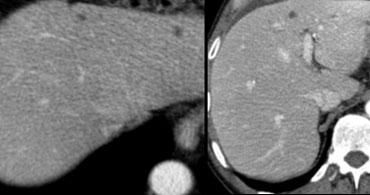

Bên trái là tổn thương không điển hình, biểu hiện giảm sinh mạch trên CT, có thể là di căn.

Cùng ca bệnh trên MR động học.

Lưu ý cách MR thể hiện rõ kiểu ngấm thuốc ngoại vi dạng nốt, lan dần vào trung tâm (mũi tên cong màu xanh) mà CT không thể hiện được.